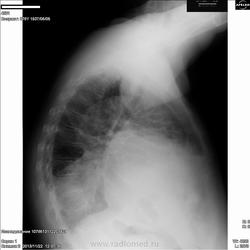

Пациентка, 76 лет. Жалобы на одышку. На кашель не жалуется. Температура нормальная. На ногах отеки.

Предполжу, все таки, прав. гидроторакс вследствие ЗНО правого легкого.

Думаю, не всё укладывается в гидроторакс. В первую очередь предположил бы рак. Либо периферический с метастазами в средостение, либо центральный. На боковом снимке больше данных за ателектаз н/д. В десятке на фоне затенения просматривается кругляш. Да и корень правого легкого ушел вниз.

Правосторонний выпот, возможно сопутствующий раку легкого или раку молочной железы.

Надо будет поискать опухоль правого лёгкого.Выпот вторичен.

При таком объёме выпота, пусть, и осумкованного внимание обращает смещение средостение вправо. С поправкой на неидеальную укладку, но есть оно. Дополнил бы УЗИ правой плевральной полости. Но гиповентиляцию справа бы тоже не исключил.